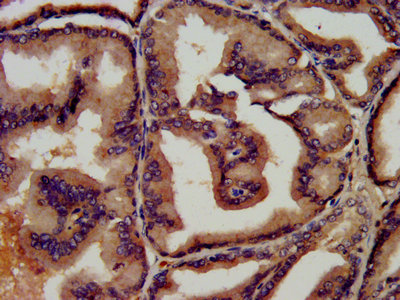

• IHC image of CSB-PA00870E0Rb diluted at 1:450 and staining in paraffin-embedded human prostate tissue performed on a Leica BondTM system. After dewaxing and hydration, antigen retrieval was mediated by high pressure in a citrate buffer (pH 6.0). Section was blocked with 10% normal goat serum 30min at RT. Then primary antibody (1% BSA) was incubated at 4°C overnight. The primary is detected by a biotinylated secondary antibody and visualized using an HRP conjugated SP system.